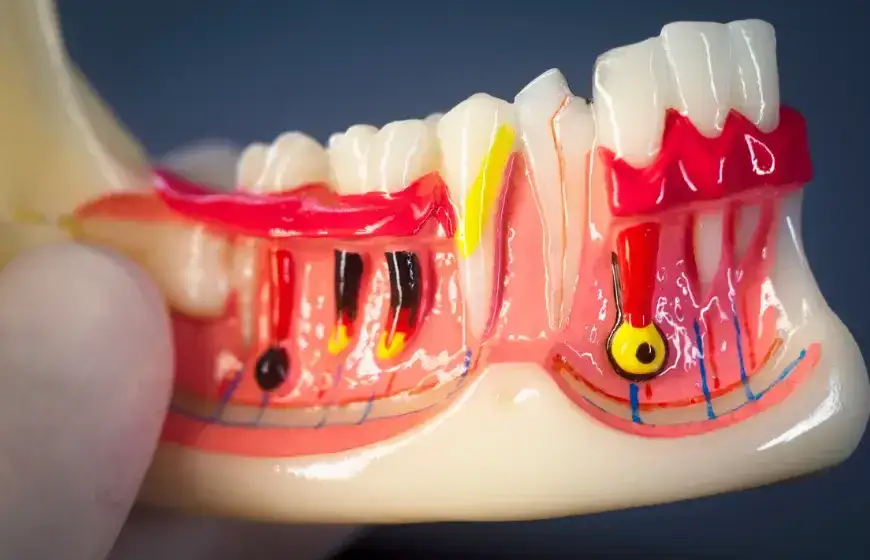

Uszkodzenie miazgi zębowej – jak się objawia?

Uszkodzenie miazgi zębowej jest poważnym powikłaniem, które może wystąpić w przypadku pionowego pęknięcia korzenia zęba. Objawy tego schorzenia często obejmują silny ból, który może być odczuwany jako pulsujący lub ostry, zwłaszcza podczas gryzienia. Pacjenci mogą również doświadczać nadwrażliwości na ciepło i zimno, co wskazuje na stan zapalny miazgi. W niektórych przypadkach, uszkodzenie miazgi może prowadzić do martwicy, co oznacza, że ząb traci swoje naturalne funkcje i wymaga interwencji dentystycznej.